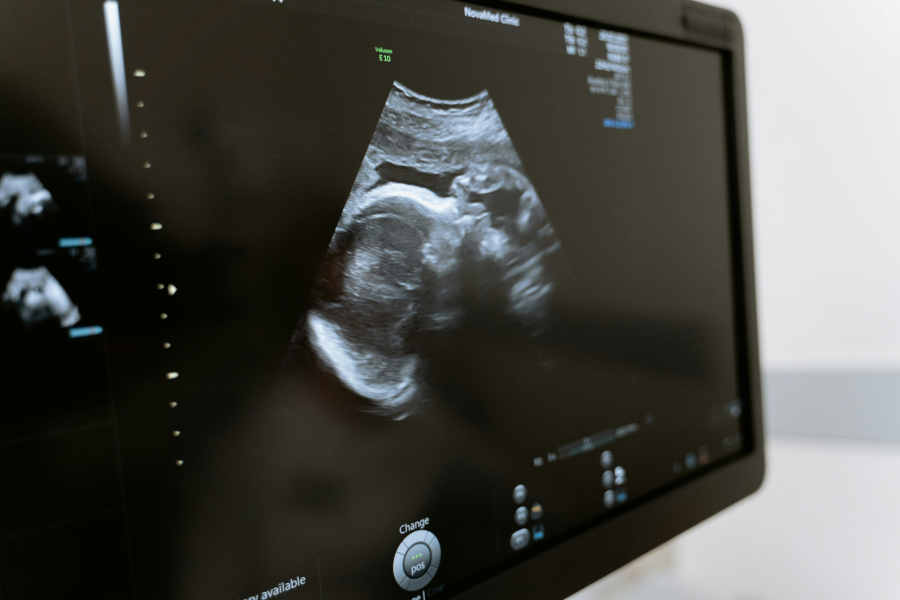

Κατόπιν αυτού, με την υποστήριξη και της οικογένειάς της, η 34χρονη γυναίκα αποφάσισε να προχωρήσει στο επόμενο βήμα, επιδιώκοντας μια εγκυμοσύνη με μεταφορά των ήδη κρυοσυντηρημένων γονιμοποιημένων ωαρίων. Η εξωσωματική γονιμοποίηση που ακολούθησε ήταν επιτυχής και η κύηση είναι πλέον σε εξέλιξη.

«Η περίπτωσή της αποτελεί την πρώτη αναφορά επιτυχούς εγκυμοσύνης στην Ελλάδα, μετά από ενδοσκοπική συντηρητική χειρουργική θεραπεία καρκίνου ενδομητρίου στην οποία διατηρήθηκε η μήτρα και οι ωοθήκες της ασθενούς. Πρόκειται, ουσιαστικά, για ένα διπλό δώρο ζωής για κάθε γυναίκα που πέρασε τη δοκιμασία της και σηματοδοτεί το μέλλον», τονίζει ο καθηγητής Γρηγόριος Γκριμπίζης.